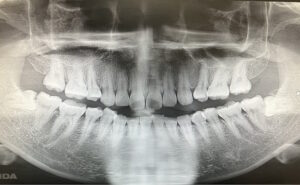

ホワイトニング治療例(30代 女性)_0002

ホワイトニング前後の比較

Before

After

• 治療内容 ホワイトニング